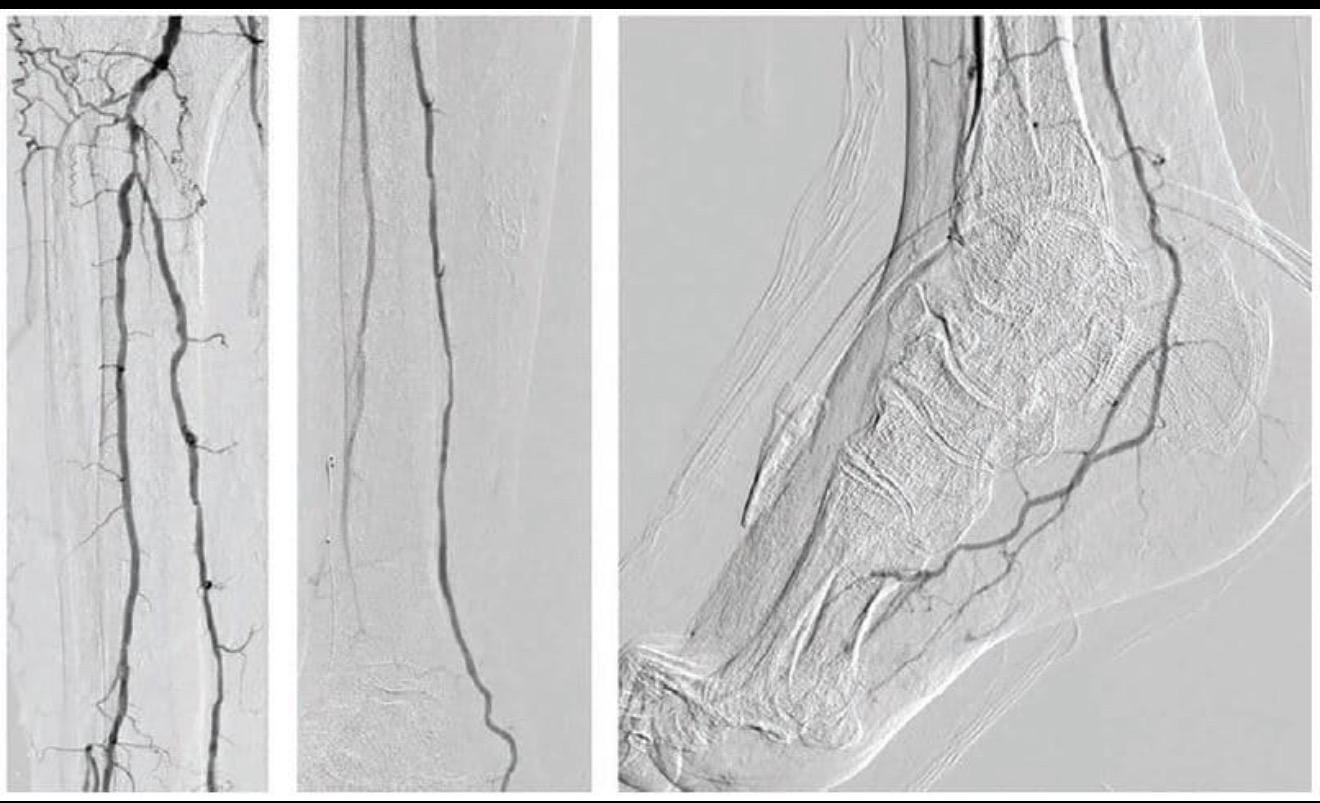

Periferik anjiyo, kasıktan girilerek bacak damarlarının görüntülenmesi ve aynı seansta tedavi edilmesidir.

* Diz altı (BTK) damarlar hedeflenir

* İnce damar teknikleri gerekir (ileri deneyim şart)

* Yaraya giden kan akımı artırılır

* Yara iyileşmesi hızlanır

* Ampütasyon riski ciddi oranda azalır